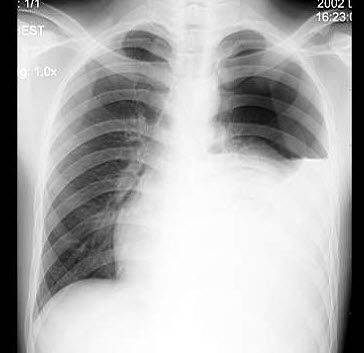

5、单项选择题

女,51岁,胸闷、咳嗽、咳痰2月余,3年前被确诊为子宫平滑肌肉瘤,结合胸片,最可能的诊断是()

A.粟粒型肺结核

B.肺转移瘤

C.结节病

D.胶原病

E.真菌病